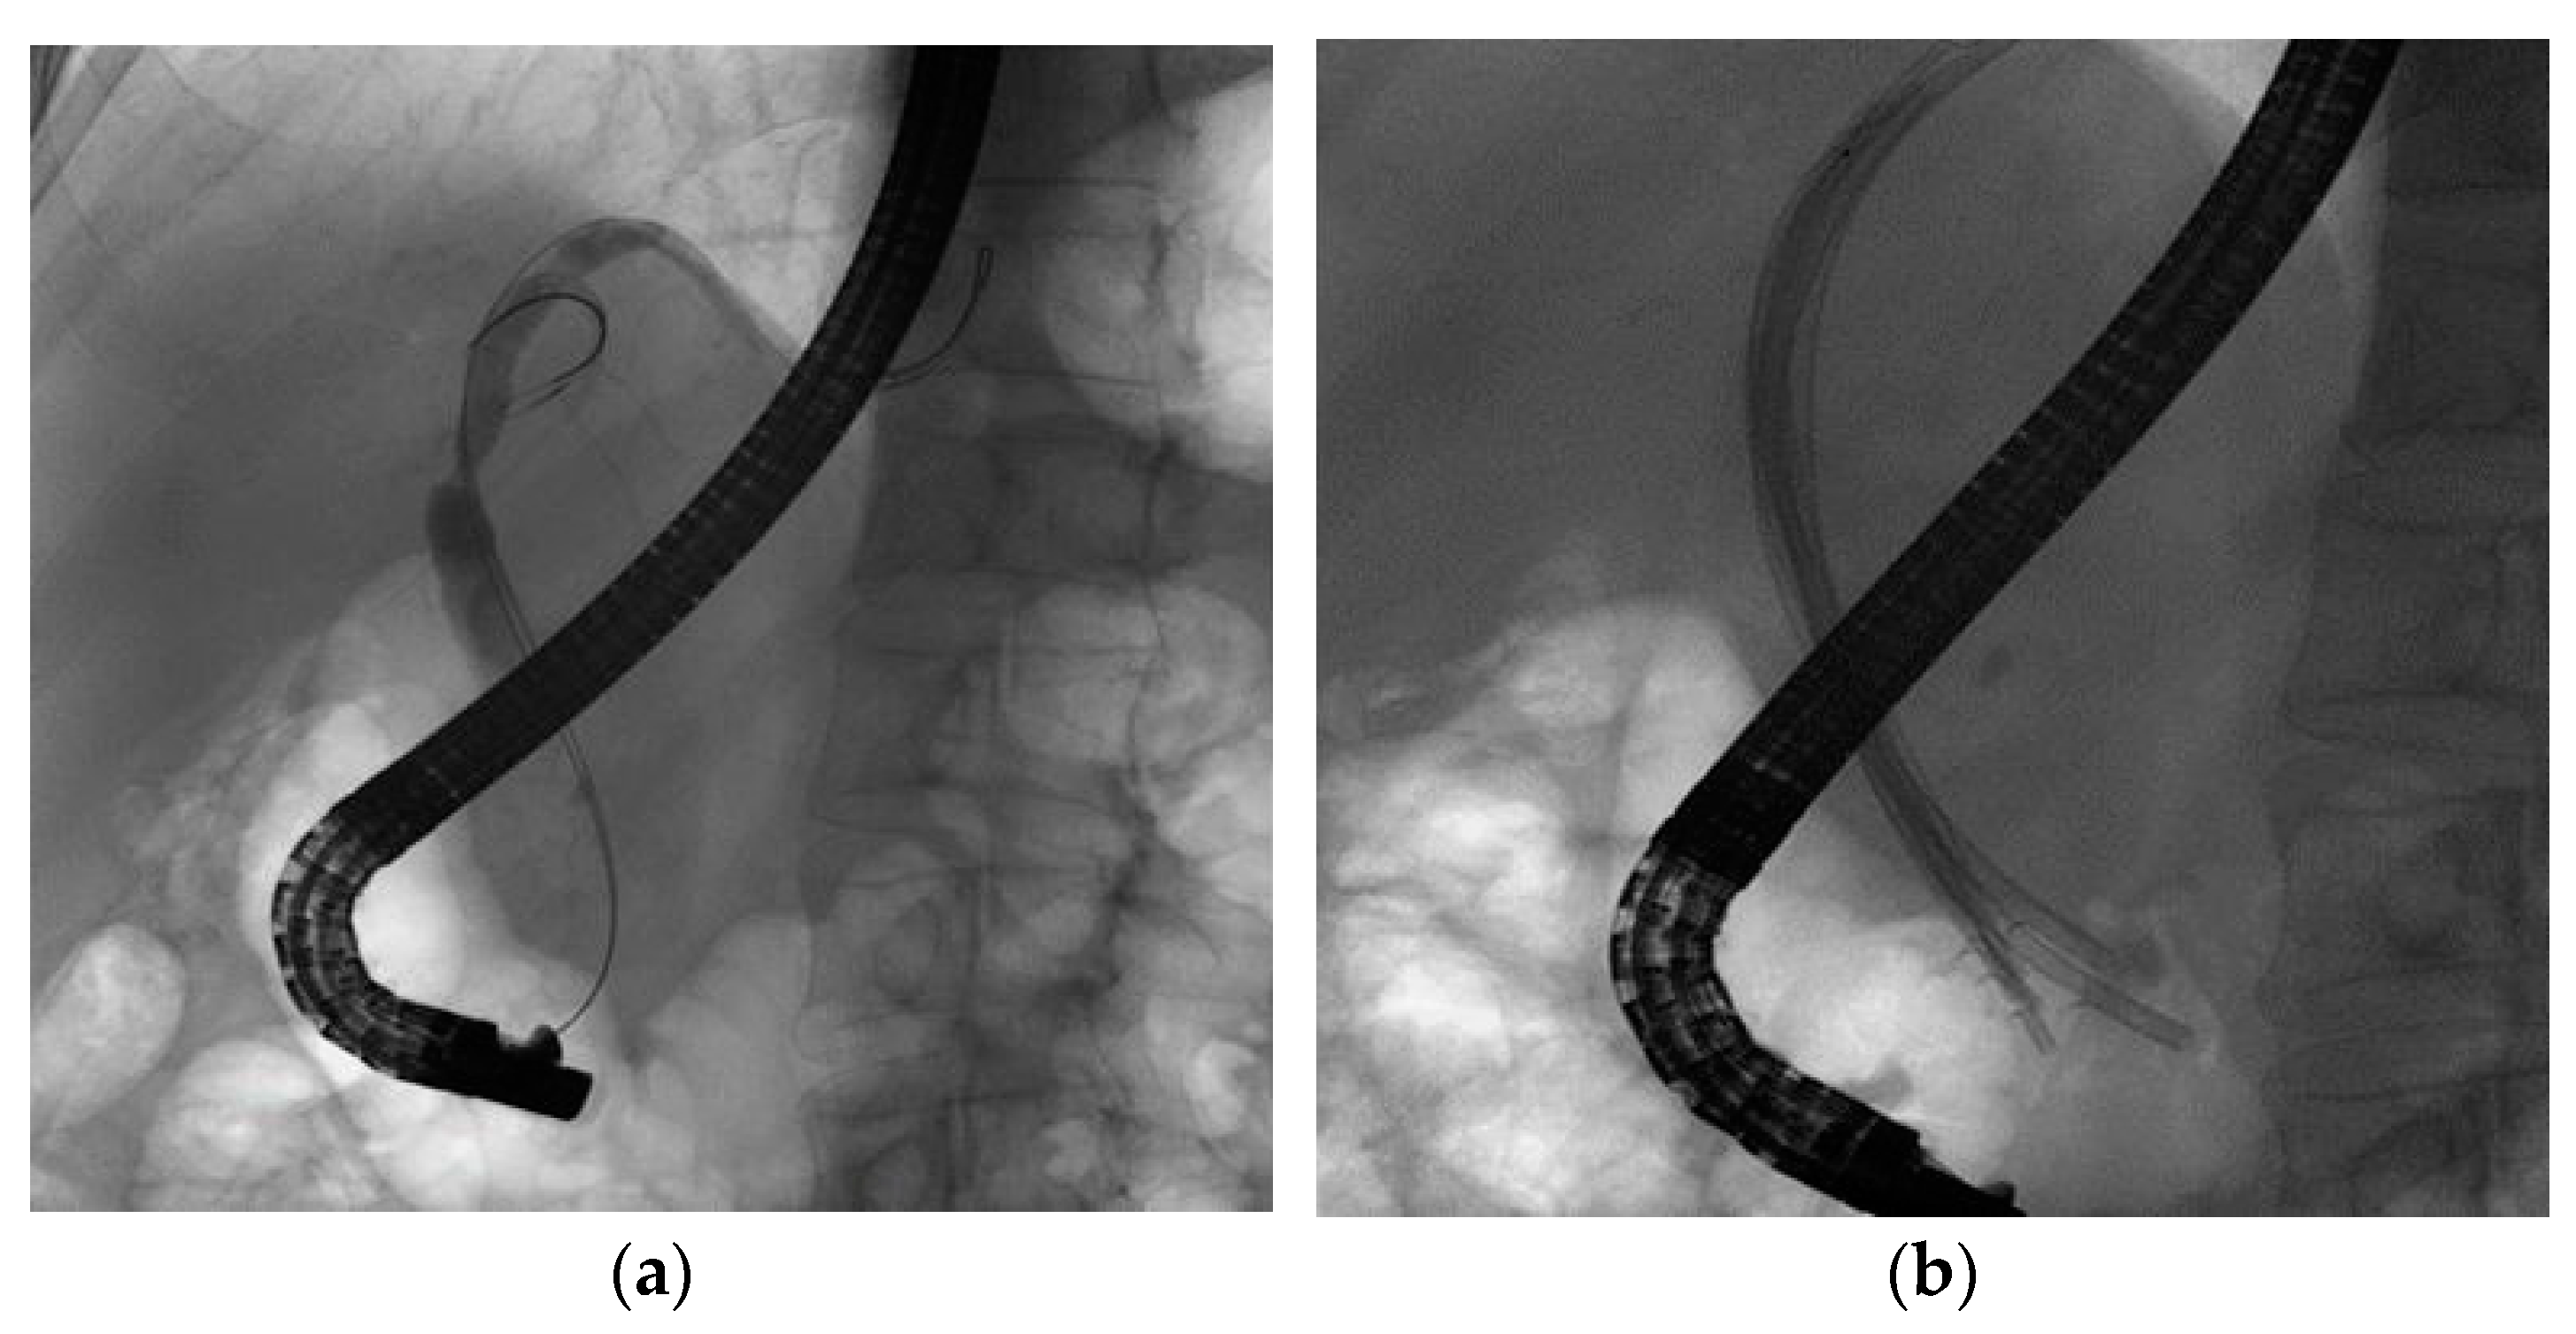

2.2. Procedure